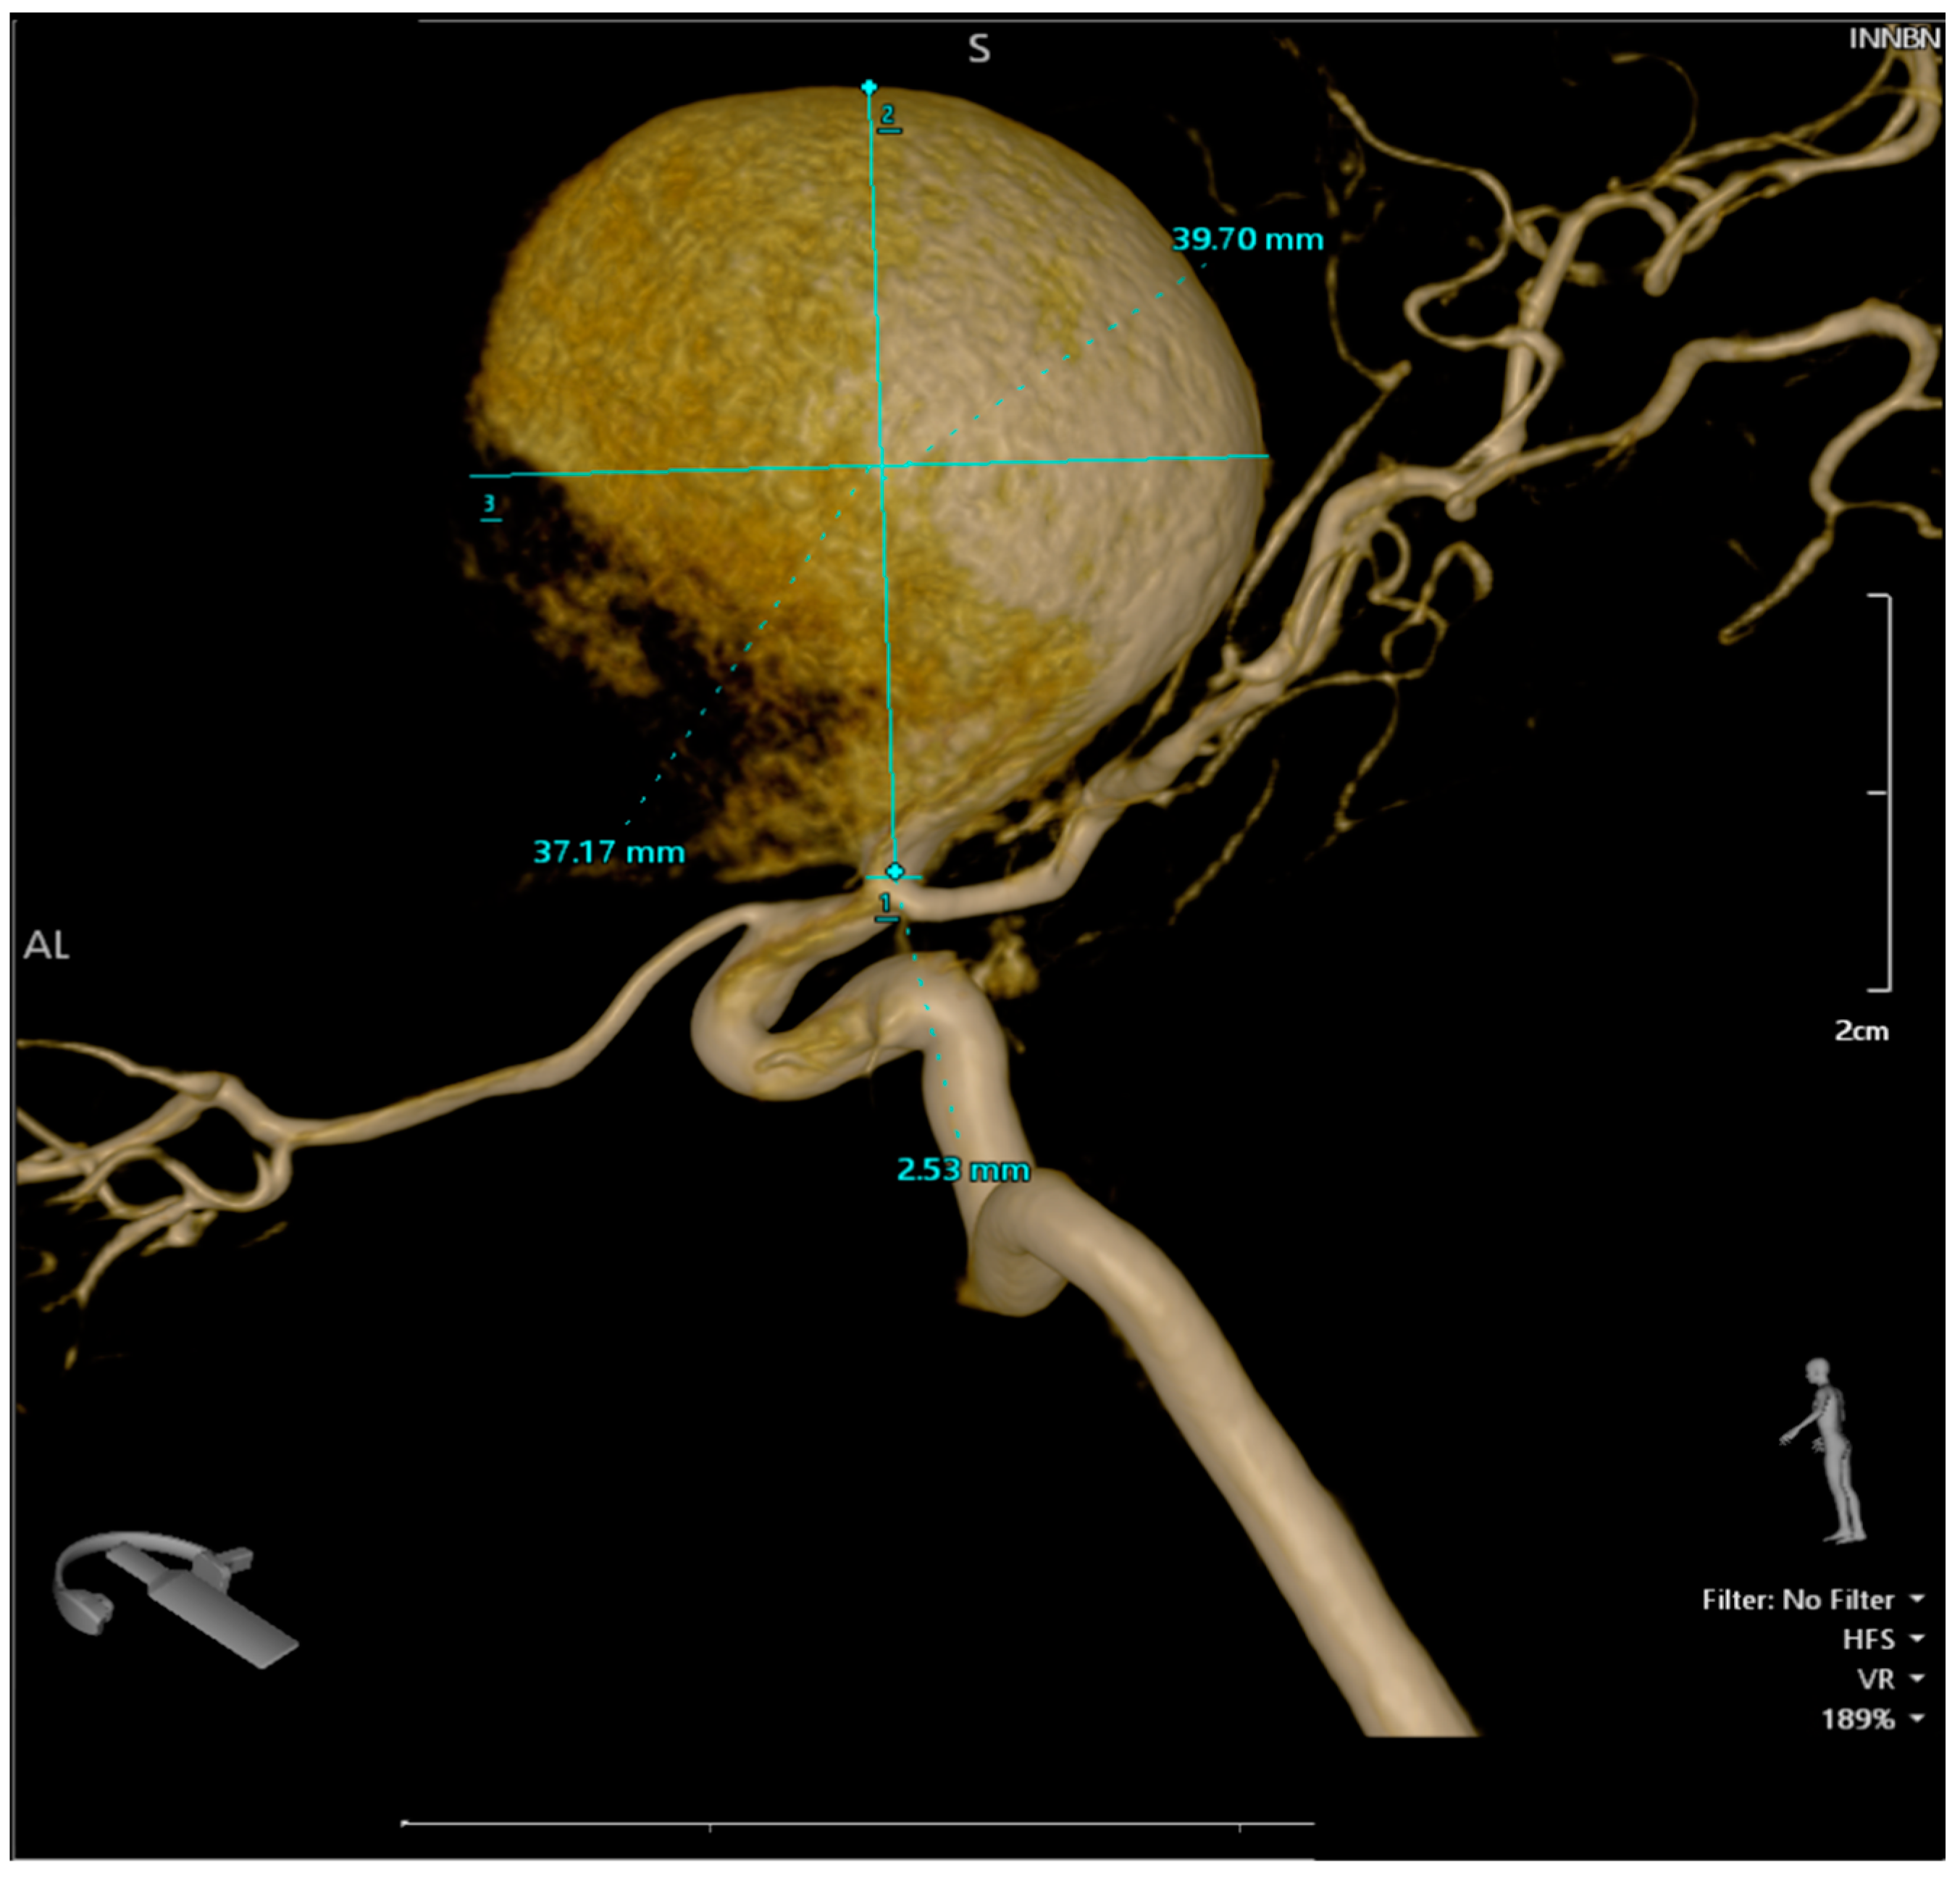

Figure 3.

The 3D reconstruction of the rotational DSA illustrating a giant aneurysm with dimensions of 4 × 3.75 cm, located at the bifurcation of the right internal carotid artery, encompassing the M1 segment of the right middle cerebral artery.